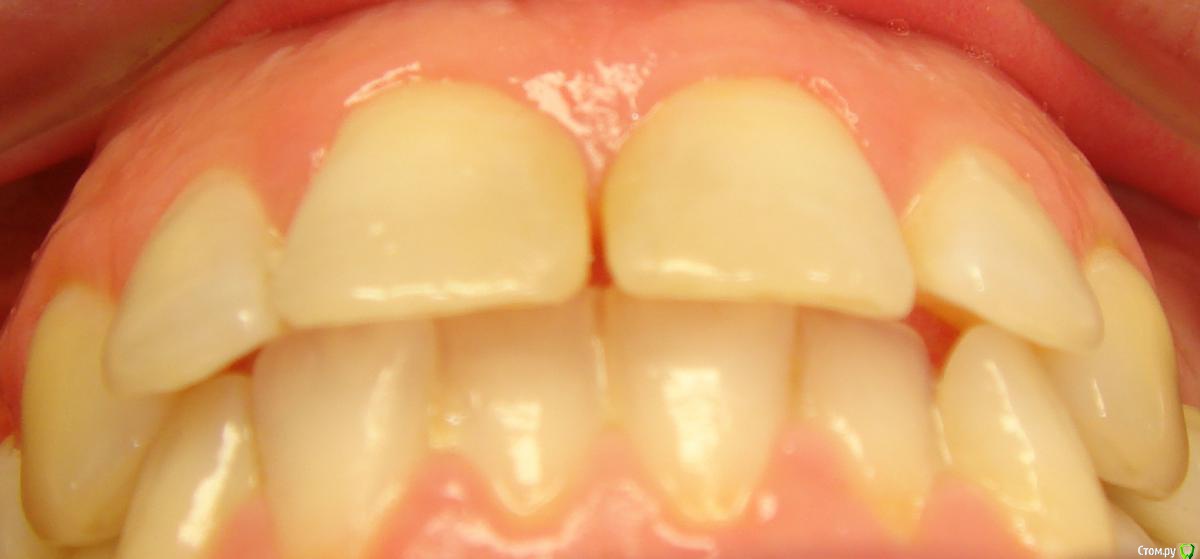

Opdihatop Опубликовано 16 апреля, 2017 Автор Поделиться Опубликовано 16 апреля, 2017 Она сама то что хочет Черные треугольники заполнить и рецессии убрать. Ссылка на комментарий

Brigita Опубликовано 16 апреля, 2017 Поделиться Опубликовано 16 апреля, 2017 Черные треугольники заполнить и рецессии убрать. я вот чего то не понимаю наверно.. где треугольники, которые она хочет убрать? я вижу диастему, трему 22-21, кариес 11-12, многочисленные рецессии, плохие ортопедические коронки, неправильно выполненные вкладки ( а может правильно? я не ортопед), скученность нижних зубов. А вообще вот интересно - в каком возрасте максимально возможно расширение на SARPE, у кого какой опыт? Ссылка на комментарий

Opdihatop Опубликовано 17 апреля, 2017 Автор Поделиться Опубликовано 17 апреля, 2017 где треугольники Я имел ввиду щечные коридоры. Неправильно назвал, все-таки праздник был. Ссылка на комментарий